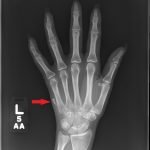

Glass Foreign Body Hand Radiograph

Significant findings:

Left hand plain radiography demonstrated a subcutaneous foreign body medial to the 5thmetacarpal that is radiopaque, trapezoidal in shape, and measures approximately 11mm x 3mm.